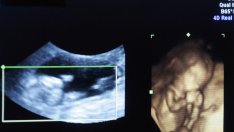

Снимка: Sxc.hu